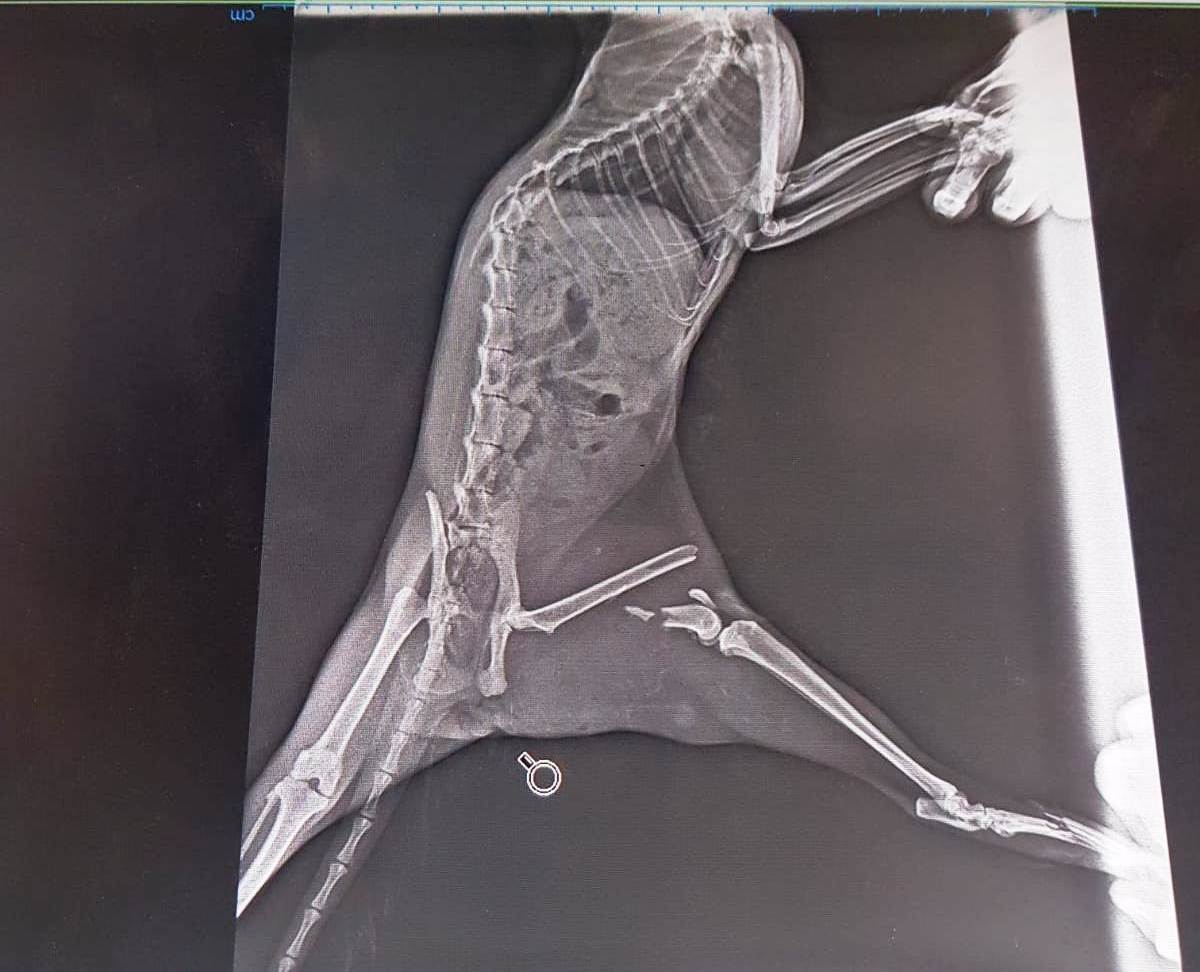

İznik Belediyesi Veteriner Hekimi Mertkan Bahçekapılı’nın yaptığı açıklamada “Kediye yaptığımız ilk müdahalede durumu ağırdı. Anında müdahale ederek röntgenlerini çektik. Röntgen çekimlerinde arka sol ayağında zor bir kırık olduğunu tespit ettik. Bu röntgen sırasında bir de yavrusu olduğunu gördük. Kendisine platin yaparak taktık.1 aydır gözetimimiz altında olan kedi geçtiğimiz gün bir yavru dünyaya getirdi. Şuanda yavru ve anne gayet sağlıklı, bir süre daha gözetimimiz altında duracak” dedi.